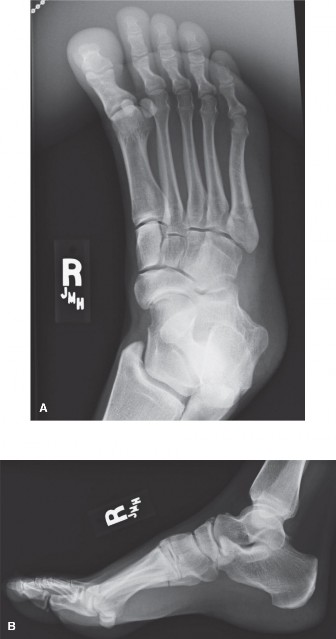

CASE Dr. Melinda Sharkey A 10-day-old male is brought into your office for evaluation of foot deformities. Th…

A healthy 43-year-old female developed insidious onset of plantar right heel pain 2 months ago. She describes…